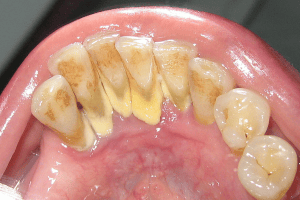

Ngoài ra, sự tích tụ của chất bám và vi khuẩn trên bề mặt răng cũng là một trong những yếu tố gây ra tình trạng này. Vi khuẩn trong miệng của chúng ta sẽ tiếp xúc với thực phẩm và nước bọt, tạo thành một lớp chất bám dính trên bề mặt răng. Nếu không được vệ sinh đúng cách, lớp chất bám này sẽ dần dần tích tụ và trở nên khó loại bỏ, gây ra sự kết hợp với khoáng chất và tạo thành cao răng.

Một trong những tác hại đáng chú ý nhất của cao răng là khó khăn trong việc vệ sinh răng miệng. Các mảng bám thức ăn tích tụ và vôi hóa tại mép lợi và sát giữa các kẽ răng sẽ khiến cho chúng ta gặp khó khăn khi vệ sinh răng miệng. Bất kể chúng ta dùng tăm chỉ hay chỉ nha khoa, đều sẽ đều bị cản trở và không lấy hết được các mảnh vụn trong các kẽ răng. Nếu để tình trạng này diễn ra lâu dài, cao răng sẽ ngày càng tăng lên, dẫn đến sự hình thành của sâu răng và các vấn đề khác cho sức khỏe răng miệng.

Ngoài ra, cao răng còn gây ra tác hại về mặt thẩm mỹ. Khi được tích tụ dần dần, từng lớp và ngày một dày lên, lượng cao dày bám ở mép lợi, với màu trắng đục hoặc vàng sẽ gây mất thẩm mỹ cho răng miệng của bạn. Khi đó, bạn dễ dàng cảm thấy tự ti khi tiếp xúc với người khác và không được thoải mái. Hơn nữa, cao răng cũng có thể gây ra tình trạng hôi miệng. Cao răng tích tụ tại răng bị vôi hóa sẽ tạo ra mùi hôi khó chịu. Nếu tình trạng nặng và kéo dài, nó sẽ khiến cho chúng ta luôn cảm thấy e ngại khi nói chuyện với người khác.

Viêm lợi và các bệnh về nướu là những vấn đề rất phổ biến trong sức khỏe răng miệng của con người. Cao răng là nơi tích tụ vi khuẩn, nếu không vệ sinh sạch sẽ và lấy cao răng thường xuyên, vi khuẩn tại đó sẽ gây nên bệnh viêm lợi và viêm quanh răng. Điều này có nghĩa là cao răng không phải nguyên nhân trực tiếp gây ra các bệnh lý về răng miệng, nhưng nó là nơi trú ngụ của vi khuẩn, tạo điều kiện cho vi khuẩn gây nên các bệnh liên quan.

Viêm lợi là một trong những bệnh phổ biến nhất liên quan đến vấn đề nướu. Viêm lợi có thể gây ra các triệu chứng như sưng, tấy đỏ và chảy máu ở lợi. Nếu không được điều trị kịp thời, viêm lợi có thể tiến triển thành các bệnh nặng hơn như viêm nha chu. Viêm nha chu là một bệnh lý thường gặp ở nướu, làm cho các mô nha chu suy yếu và không thể nâng đỡ và giữ ổn định răng trên cung hàm. Điều này có thể dẫn đến các triệu chứng như đau nhức, răng lung lay và thậm chí rụng răng.